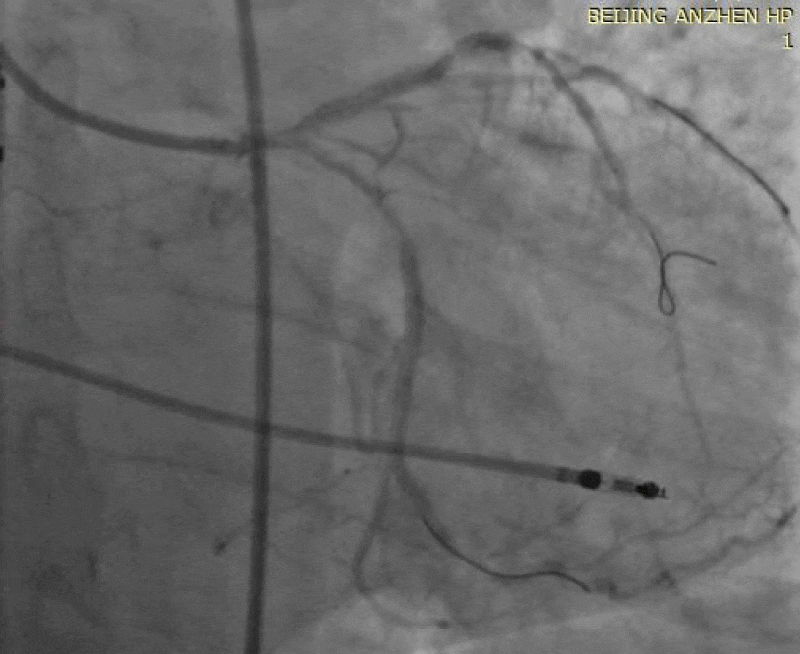

Patients were treated with PCI. Through 6F XB 3.5 guiding catheter, REGATTA guide wire was sent to the distal LAD, Runthrough guide wire was sent to the distal D, the mid LAD lesion was dilated with the B. Braun Melsungen 2.0mm×20mm balloon at 20atm. Balloon rupture occurred on the second dilatation at 20atm, leading to extravasation of contrast agent, coronary artery dissection and subintimal hematoma, dissection and hematoma extended to D, the distal left circumflex (LCX) and the proximal LAD. Cordis guide wire were immediately sent to the distal LCX, the Medtronic 2.25mm×18mm stent was deployed into the middle of LAD with the pressure of 16atm, Boston Scientific 2.25mm×32mm stent was deployed from OM3 to the mid LCX with the pressure of 14atm, entrance and exit of the dissection and hematoma were all blocked, and the dissection and hematoma was not visible. Then Cordis 2.5mm×10mm balloon was inflated to 26atm inside the LAD stent, Boston Scientific 2.25mm×12mm stent was released in the distal LAD at 10atm, the angiography showed that the stenosis was relieved, the blood flow was TIMI-3, there was no hematoma and dissection, and the patient was stable after operation.

Five hours later, the patient suddenly developed chest pain accompanied by sweat and pale, with blood pressure of 150/70mmHg. The patient was given ECG monitoring, oxygen inhalation and intravenous access. Seventeen minutes later, the patient experienced loss of consciousness and ECG showed ventricular fibrillation. The patient recovered consciousness after defibrillation and simple ventilator assisted breathing, blood pressure was 80 / 50mmHg, then the patient was turned into the cath lab for emergency PCI. After the patient entered the cath lab, ventricular fibrillation occurred again. Defibrillation treatment was performed for the second time, the patient received PCI treatment under continuous chest compression. After puncturing the right femoral artery, the 6F JL4.0 guiding catheter was placed at the LCA opening, coronary angiography showed LCX occluded, LAD still had blood flow. Runthrough guide wire was sent to the distal LCX, another Runthrough guide wire was sent to the distal LAD, the Medtronic 2.5mm × 15mm balloon was carried retracement, coronary angiography showed the mild LCX hematoma extension made LCX occluded, Medtronic 2.5mm×15mm balloon was dilated at 8-10atm from the proximal LCX to the LCX stent, coronary angiography showed that the blood flow of LCX recovered. Then puncturing the left femoral artery, intra-aortic balloon pump (IABP) balloon was implanted into the descending aorta, heart rate restored to 40 times per minute. Then the operator sent PACEL temporary pacing catheter to the right ventricular apex, the patient received temporary pacing therapy with frequency of 80 times per minute. During the treatment, the patient was given intravenous injection of 1mg epinephrine and 1mg atropine, and was given intravenous drip of 5% sodium bicarbonate, blood pressure was remained at 80-100mmHg, about 20 minutes later the patient recovered spontaneous cardiac rhythm, blood pressure rose to 80-120/40-70mmHg. Coronary angiography showed the blood flow of LAD and LCX restored. Considering possible hematoma extension of the LCX, the Medtronic 2.25mm×18mm stent was placed into the proximal LCX with the inflation pressure of 10atm, the LEPU 2.75mm×18mm stent was placed into the proximal LAD with the inflation pressure of 14atm, the LEPU 3.5mm×15mm stent was placed from LM to LAD with the inflation pressure of 18atm, the angiography showed that all stents achieved good apposition to the wall, the blood flow was TIMI-3, there was no hematoma and dissection. The LCX opening was mild involved, considering the possibility of dissection may occur, so we did not perform kissing dilation. After operation the patient was transferred to the CCU ward for further treatment Figures 1-4.

Figure 1:

Figure 2: